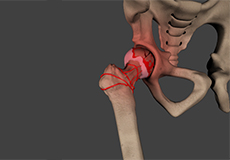

Hip Dislocation

The hip joint is a “ball and socket” joint. The “ball” is the head of the femur or thighbone, and the “socket” is the cup-shaped acetabulum.